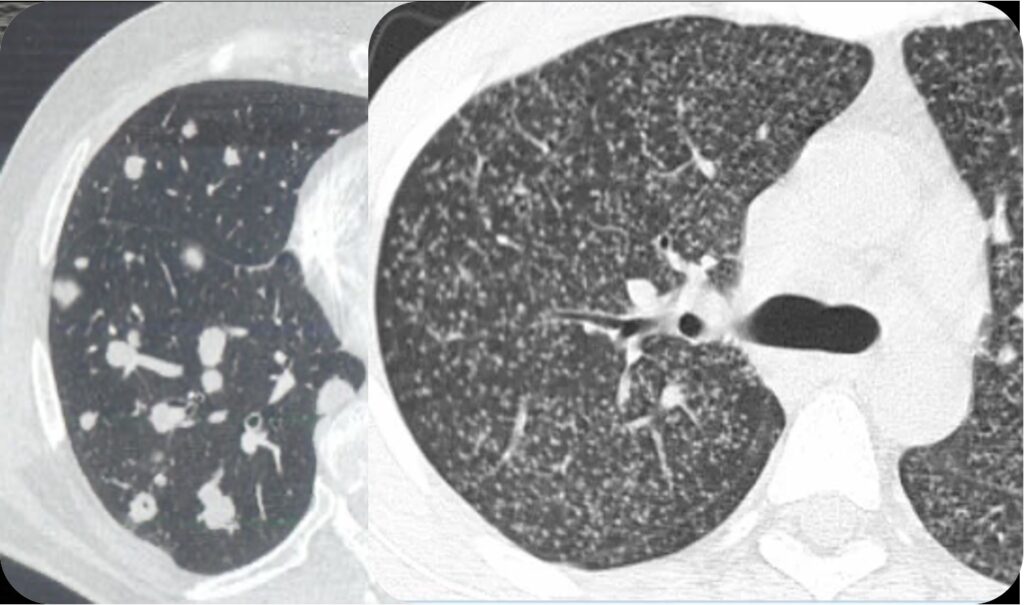

Pattern Nodulare

Pattern nodulare Il pattern nodulare è caratterizzato dalla presenza di noduli che possono variare per dimensione, distribuzione e densità. I noduli rappresentano addensamenti focali del